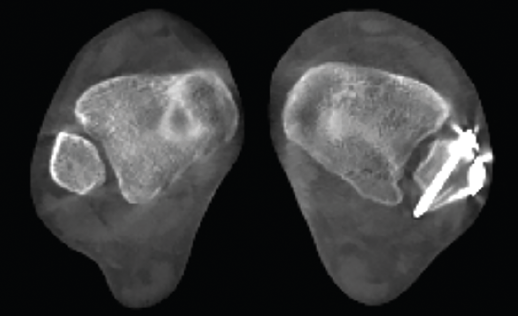

Lesiones de la sindesmosis

En la articulación tibioastragalina, la estabilidad de la articulación de la sindesmosis es un aspecto importante para evitar la aparición de lesiones articulares o artropatía progresiva.

En un contexto postraumático, la valoración de la afectación o la inestabilidad de la misma tiene su importancia para los resultados finales y los posibles tratamientos.

En la cuantificación del desplazamiento y de la inestabilidad de la sindesmosis es importante poder explorar la extremidad contralateral y la valoración en carga de los 2 tobillos.

Los estudios fisiológicos con TAC en carga muestran que el peroné presenta una rotación externa y un desplazamiento posterior con la carga(13).

La valoración inter- e intraobservador en lesiones traumáticas de la sindesmosis es mejor con la TAC en carga que con otros métodos diagnósticos(14,15).

- Alteración-inestabilidad de la sindesmosis. Permite el estudio comparativo de la estabilidad de la sindesmosis (Figuras 7 y 8).